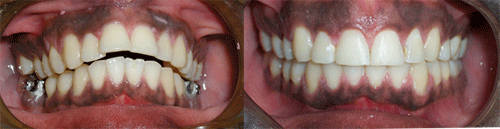

Protruded teeth (bucked teeth) happen when either the upper jaw is too far forward, the lower jaw is too far back, or a combination of both. Expert analysis allows us to determine the cause of the protrusion, and the most effective treatment plan.

With this type of bite, the front teeth are very protuded, and makes these delicate teeth highly prone to trauma, injury, and even premature tooth loss.

We have a number of different options and appliance types for correcting protruded teeth. The photos below illustrate protruded teeth, and the corrections in our patients.